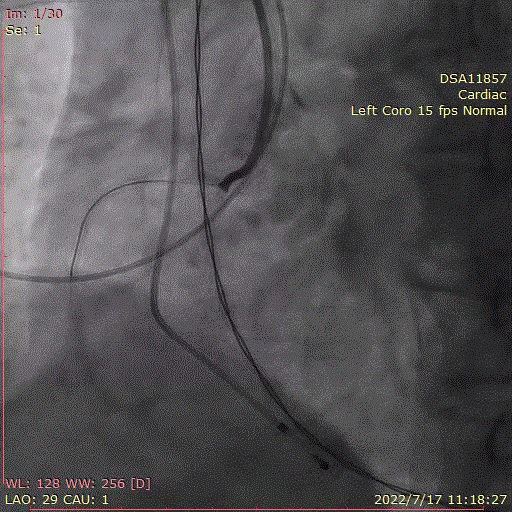

术中首先行冠脉造影术,造影提示右冠近中段严重狭窄,于病变处植入支架一枚。植入后造影显示,无残余狭窄及夹层,前向血流TIMI3级。

冠脉造影,支架植入

直头导丝跨瓣